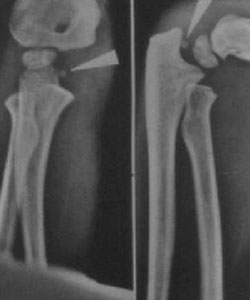

An avulsion of the medial epicondyle, also called a medial epicondyle fracture, commonly occurs in the pediatric population between the ages of 9-14 years old. This accounts for about 20% of all pediatric elbow fractures. This fracture has become more common due to the increase in the athletic demands of the pediatric population. The injury is referred to as an avulsion injury because it occurs when there is excess valgus stress with contraction of the flexor-pronator mass. The mechanism of the injury also makes it very common to occur with elbow dislocations as well. While most of these dislocations will spontaneously reduce before making it to a hospital, the medial epicondyle bony fragment can get incarcerated in the joint during the reduction. Figure 1 shows an example of an incarcerated medial epicondyle in the elbow joint after associated elbow dislocation.

Image Courtesy - https://www.orthobullets.com/pediatrics/4008/medial-epicondylar-fractures--pediatric

Figure 1